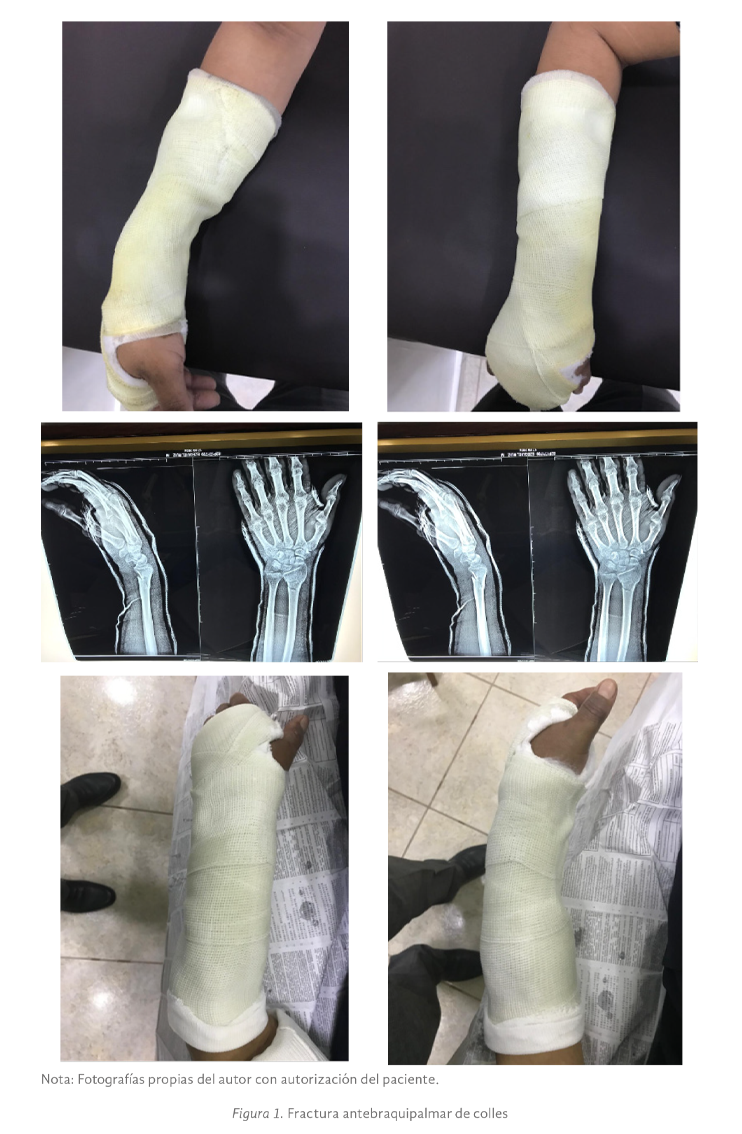

El diagnóstico de las fracturas de Colles se realiza generalmente por la clínica: dolor, deformidad, tumefacción, y realizando pruebas radiográficas (Lutza, 2004). En la figura 1 se observa el yeso antebraquipalmar en fractura de colles con manejo conservador.